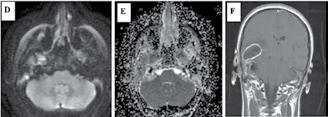

• Studiul opacifierii ramurilor corticale ale arterelor cerebrale medii (M4) drepte și stângi și a venelor cerebrale interne drepte și stângi (Fig.1).

Fig.1 ACTMS cranio-cerebrală, recon MIP în plan axial (a,b) și sagital (c): aspect normal; (a) opacifierea arterelor temporale dreaptă și stângă (săgeţi); (b) opaciferea ramurilor corticale ale arterelor cerebrale medii (M4)-săgeţi albe; opaciferea venelor cerebrale interne dreaptă și stângă (săgeţi negre-b și c).

Semiologie:

▶ Absența opacifierii M4 = 1 punct

▶ Opacifierea M4 = 0 punct

▶ Absența opacifierii venei cerebrale interne = 1 punct

▶ Opacifierea venei cerebrale interne = 0 puncte

• Un scor egal sau mai mare de 3 confirmă stopul circulator intracerebral. In acest caz, concluzia examinării este: „stop circulator intracerebral” care vine în sprijinul diagnosticului clinic de moarte cerebrală sau aspect ACT compatibil cu moartea cerebrală

• În caz contrar, concluzia examinării este „absența opririi circulatiei intracerebrale”, situaţie în care diagnosticul clinic de MC nu este confirmat.